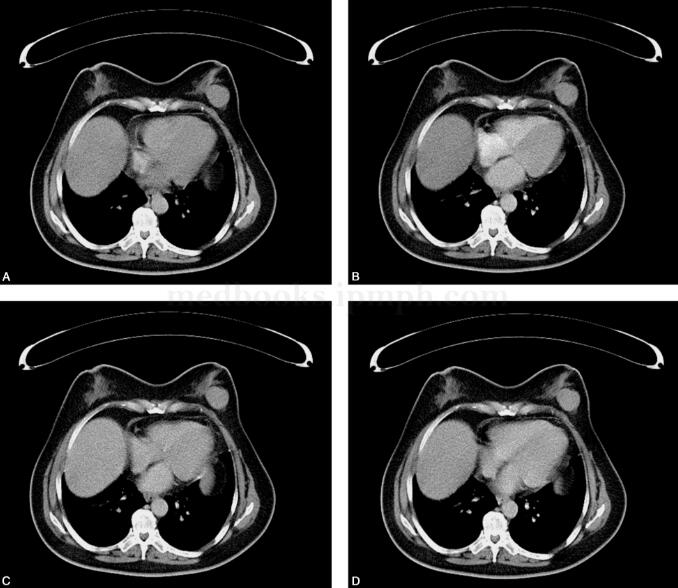

图3 双乳腺CT平扫及多期动态增强扫描(另一病例)

左乳腺外上象限可见软组织肿块影,边界尚清,呈略分叶状,CT值约30HU,截面约3.4cm×3.0cm,内部见点状钙化,增强扫描左乳肿物可见较明显强化,CT值升至58 HU,并见持续性强化